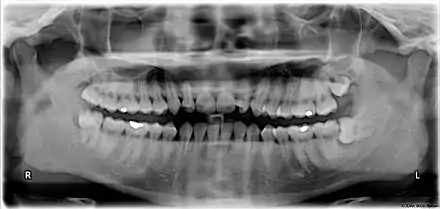

![]() Wisdom teeth in the human mouth for permanent teeth. There are none in deciduous (children's) teeth. | |

![]() Wisdom teeth | |